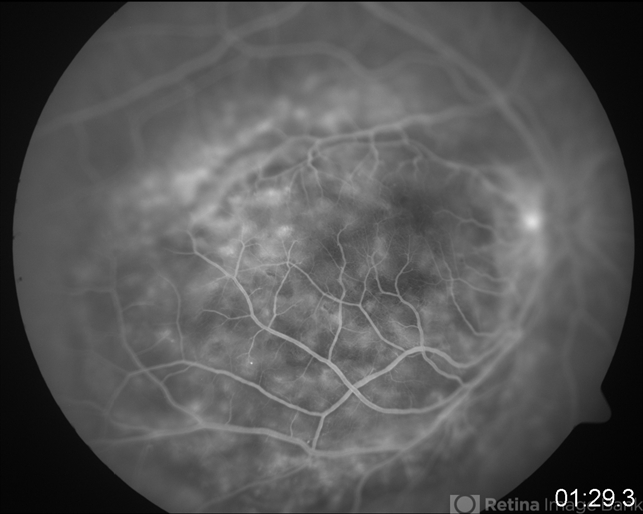

- Fundus photograph of a 62-year-old male with a choroidal melanoma on the posterior pole. Double circulation is observed.